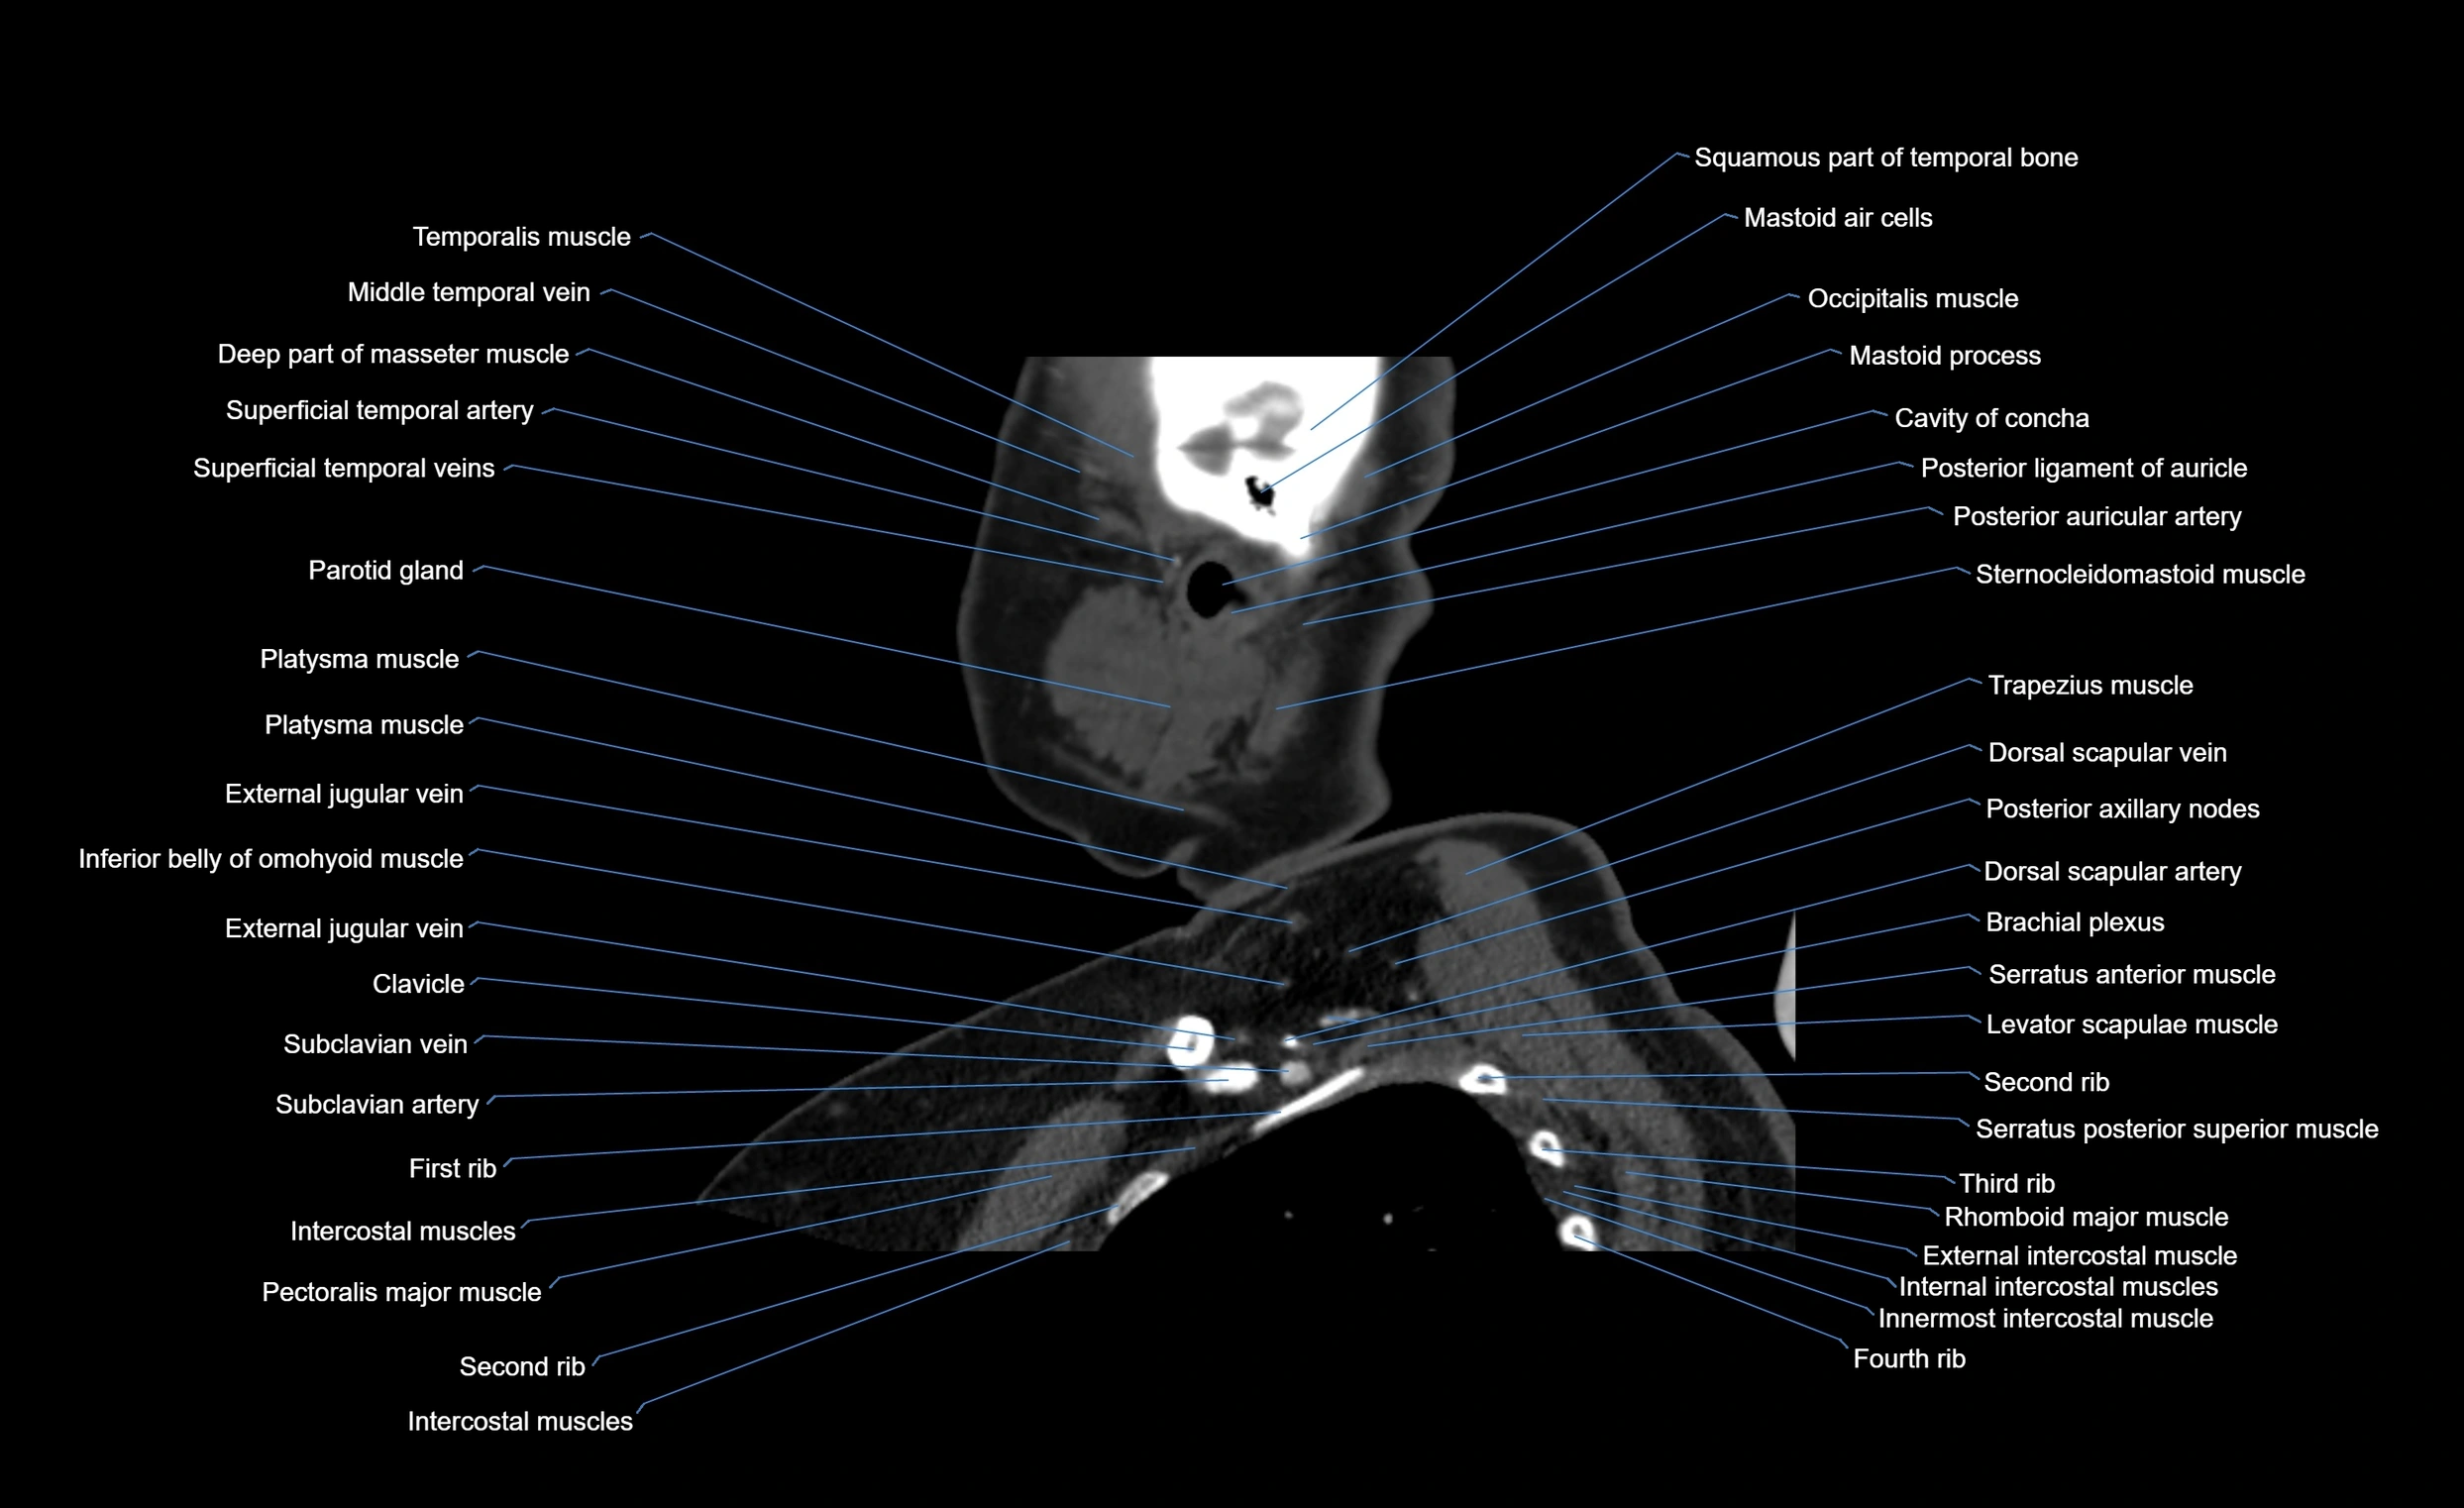

- External jugular vein

- Levator scapulae muscle

- Pectoralis major muscle

- Platysma muscle

- Rhomboid major muscle

- Serratus anterior muscle

- Serratus posterior superior muscle

- Sternocleidomastoid muscle

- Subclavian artery

- Superficial temporal artery

- Superficial temporal vein

- Temporalis muscle

- Trapezius muscle